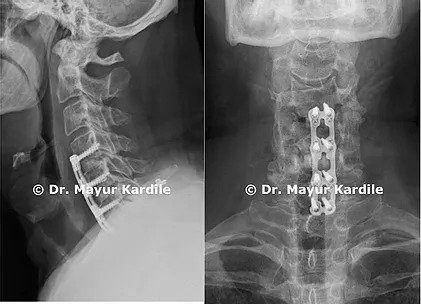

A 51-year-old gentleman complained of pain and weakness in the right arm.

MRI revealed foraminal narrowing and nerve root compression at C4-5, C5-6, C6-7

C4-5, C5-6, C6-7 Anterior cervical discectomy and fusion (ACDF) surgery was done to relieve the pressure on the cervical nerve roots.

This surgery was done through a small transverse incision over the front of the neck.

The patient regained full strength in his right arm over a period of 6 months after the surgery.